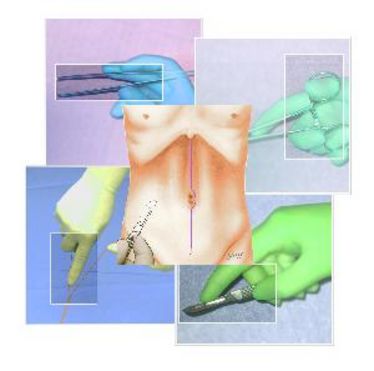

16.03.2011

- 18.03.2011

OP-Kurs "Mikrochirurgie der peripheren Nerven und Gefäße"

OP-Kurs "Mikrochirurgie der peripheren Nerven und Gefäße"